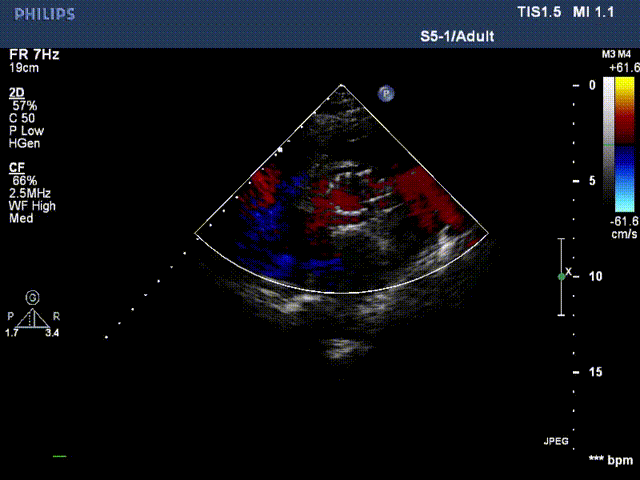

术后超声

术后超声提示:瓣膜位置良好,无漏

压差

术前跨瓣压差96mmHg,术后跨瓣压差2mmHg